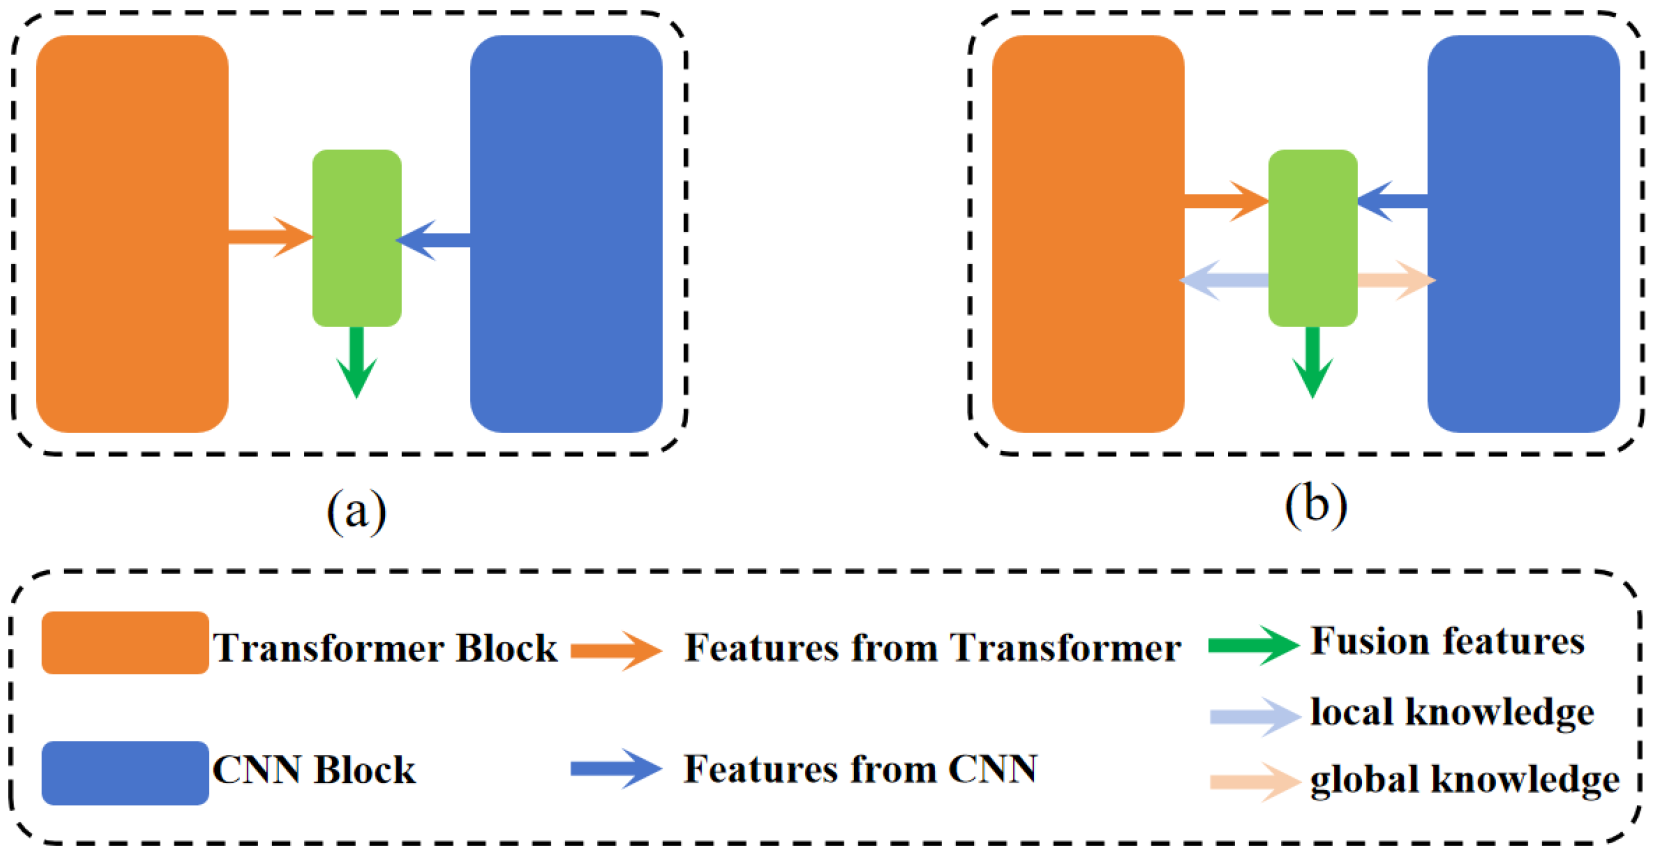

- The introduction of a novel network, DEFI-Net, notably enhancing the MIS performance through Transformer–CNN interactive learning. This interaction is facilitated by the GLIL module. The GLIL module consists of two parallel spatial attention modules: one module extracts global semantic information from the features of the Transformer encoder while the other captures local detail information from the features of the CNN encoder. Effective interaction between the two encoders is achieved by using the global semantic information to weight the features from the CNN encoder and refining the features from the Transformer encoder with local detail information.

- The development of a GLFF module that utilizes the global semantic information and local detail information produced by the GLIL module to integrate features from both the Transformer and CNN encoders. The GLFF module concatenates the features from the two encoders and employs a channel attention mechanism to enhance relevant channel features while suppressing less significant ones. The global semantic and local detail information from the GLIL module is then used to weight the concatenated features, resulting in a more precise feature representation.

2.3. Combining CNN and Transformer for MIS

3.1. Transformer–CNN Dual-Encoder

3.2. Global–Local Interaction Learning Module

3.3. Global–Local Feature Fusion Module